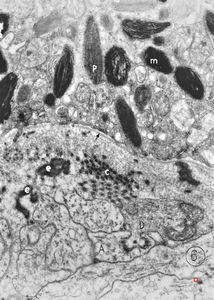

normal seromucinous salivary gland